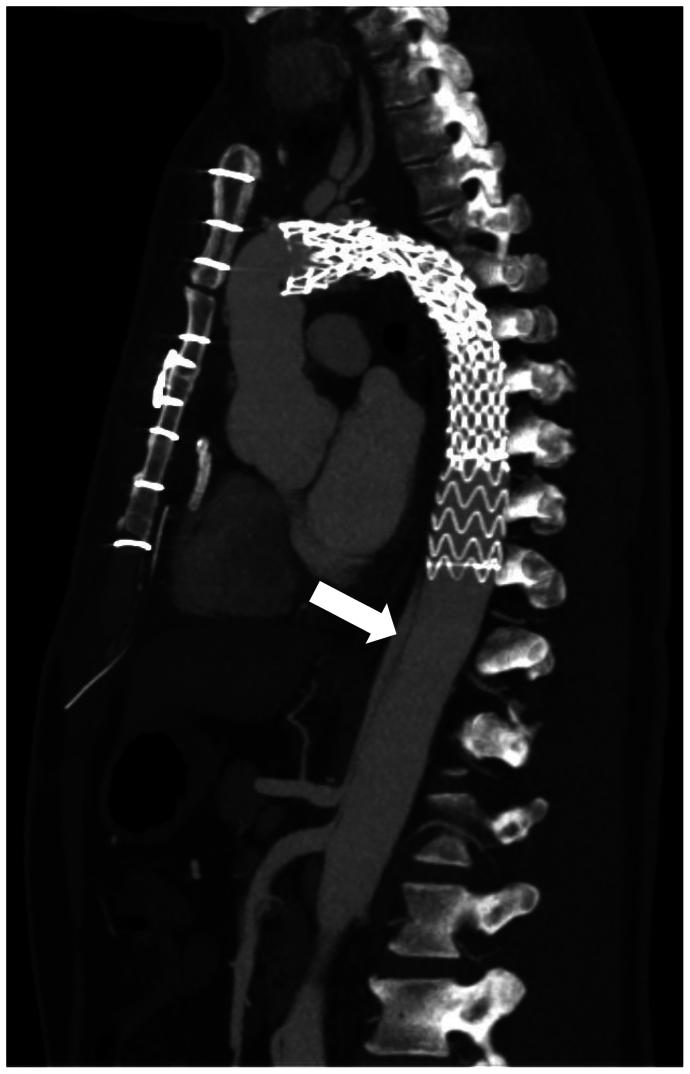

Fenestration of the septum between the true and false lumen might be necessary after aortic dissection. We report the technical aspects of in situ laser fenestration of the aortic dissection septum. Two illustrative cases are provided: a 56-year-old man with false lumen deployment of a frozen elephant trunk graft, and a 67-year-old man who underwent fenestrated endovascular aortic repair with a target branch vessel off the false lumen. In both cases, the septum was crossed using in situ laser fenestration. This technique is a precise option to enable passage between true and false lumens during endovascular repair of an aortic dissection.